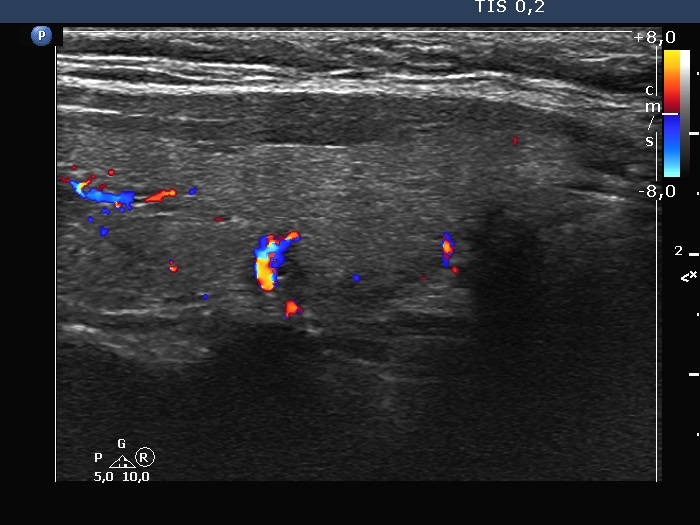

Right lobe, longitudinal scan

Right lobe, longitudinal scan, color Doppler mode. It turned out that the lesion is indeed a vessel.